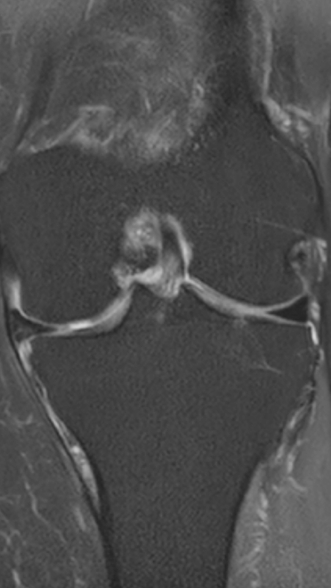

Рецидивирующий синовит коленного сустава

Излечение за 1 процедуру ФДТ Ревиксан